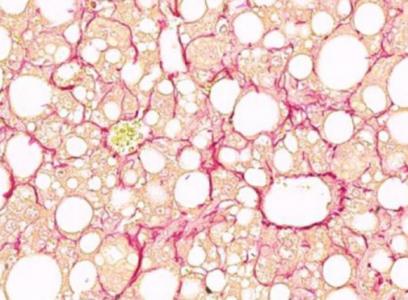

La stéatose hépatique non alcoolique (NAFLD : nonalcoholic fatty liver disease), caractérisée par l'accumulation de graisse dans le foie est la maladie du foie la plus courante dans le monde. Elle touche plus de 90% des personnes obèses, 60% des diabétiques et jusqu'à 20% des personnes de poids normal. Le foie peut « rester gras » sans perturbation de sa fonction normale mais cet état peut également évoluer vers une stéatohépatite non alcoolique, une forme plus agressive de stéatose hépatique associée à une inflammation et à une fibrose, une condition qui peut à son tour évoluer vers la cirrhose puis le cancer du foie et le décès. Sans rapport avec la consommation d'alcool par définition, le premier stade de la stéatose hépatique non alcoolique est asymptomatique.

La fibrose hépatique est un puissant prédicteur de mortalité à long terme chez les patients atteints de stéatose hépatique non alcoolique. Les mécanismes sous-jacents à la progression de la stéatose hépatique vers la stéatohépatite non alcoolique avancée et la fibrose hépatique restent encore mal compris.